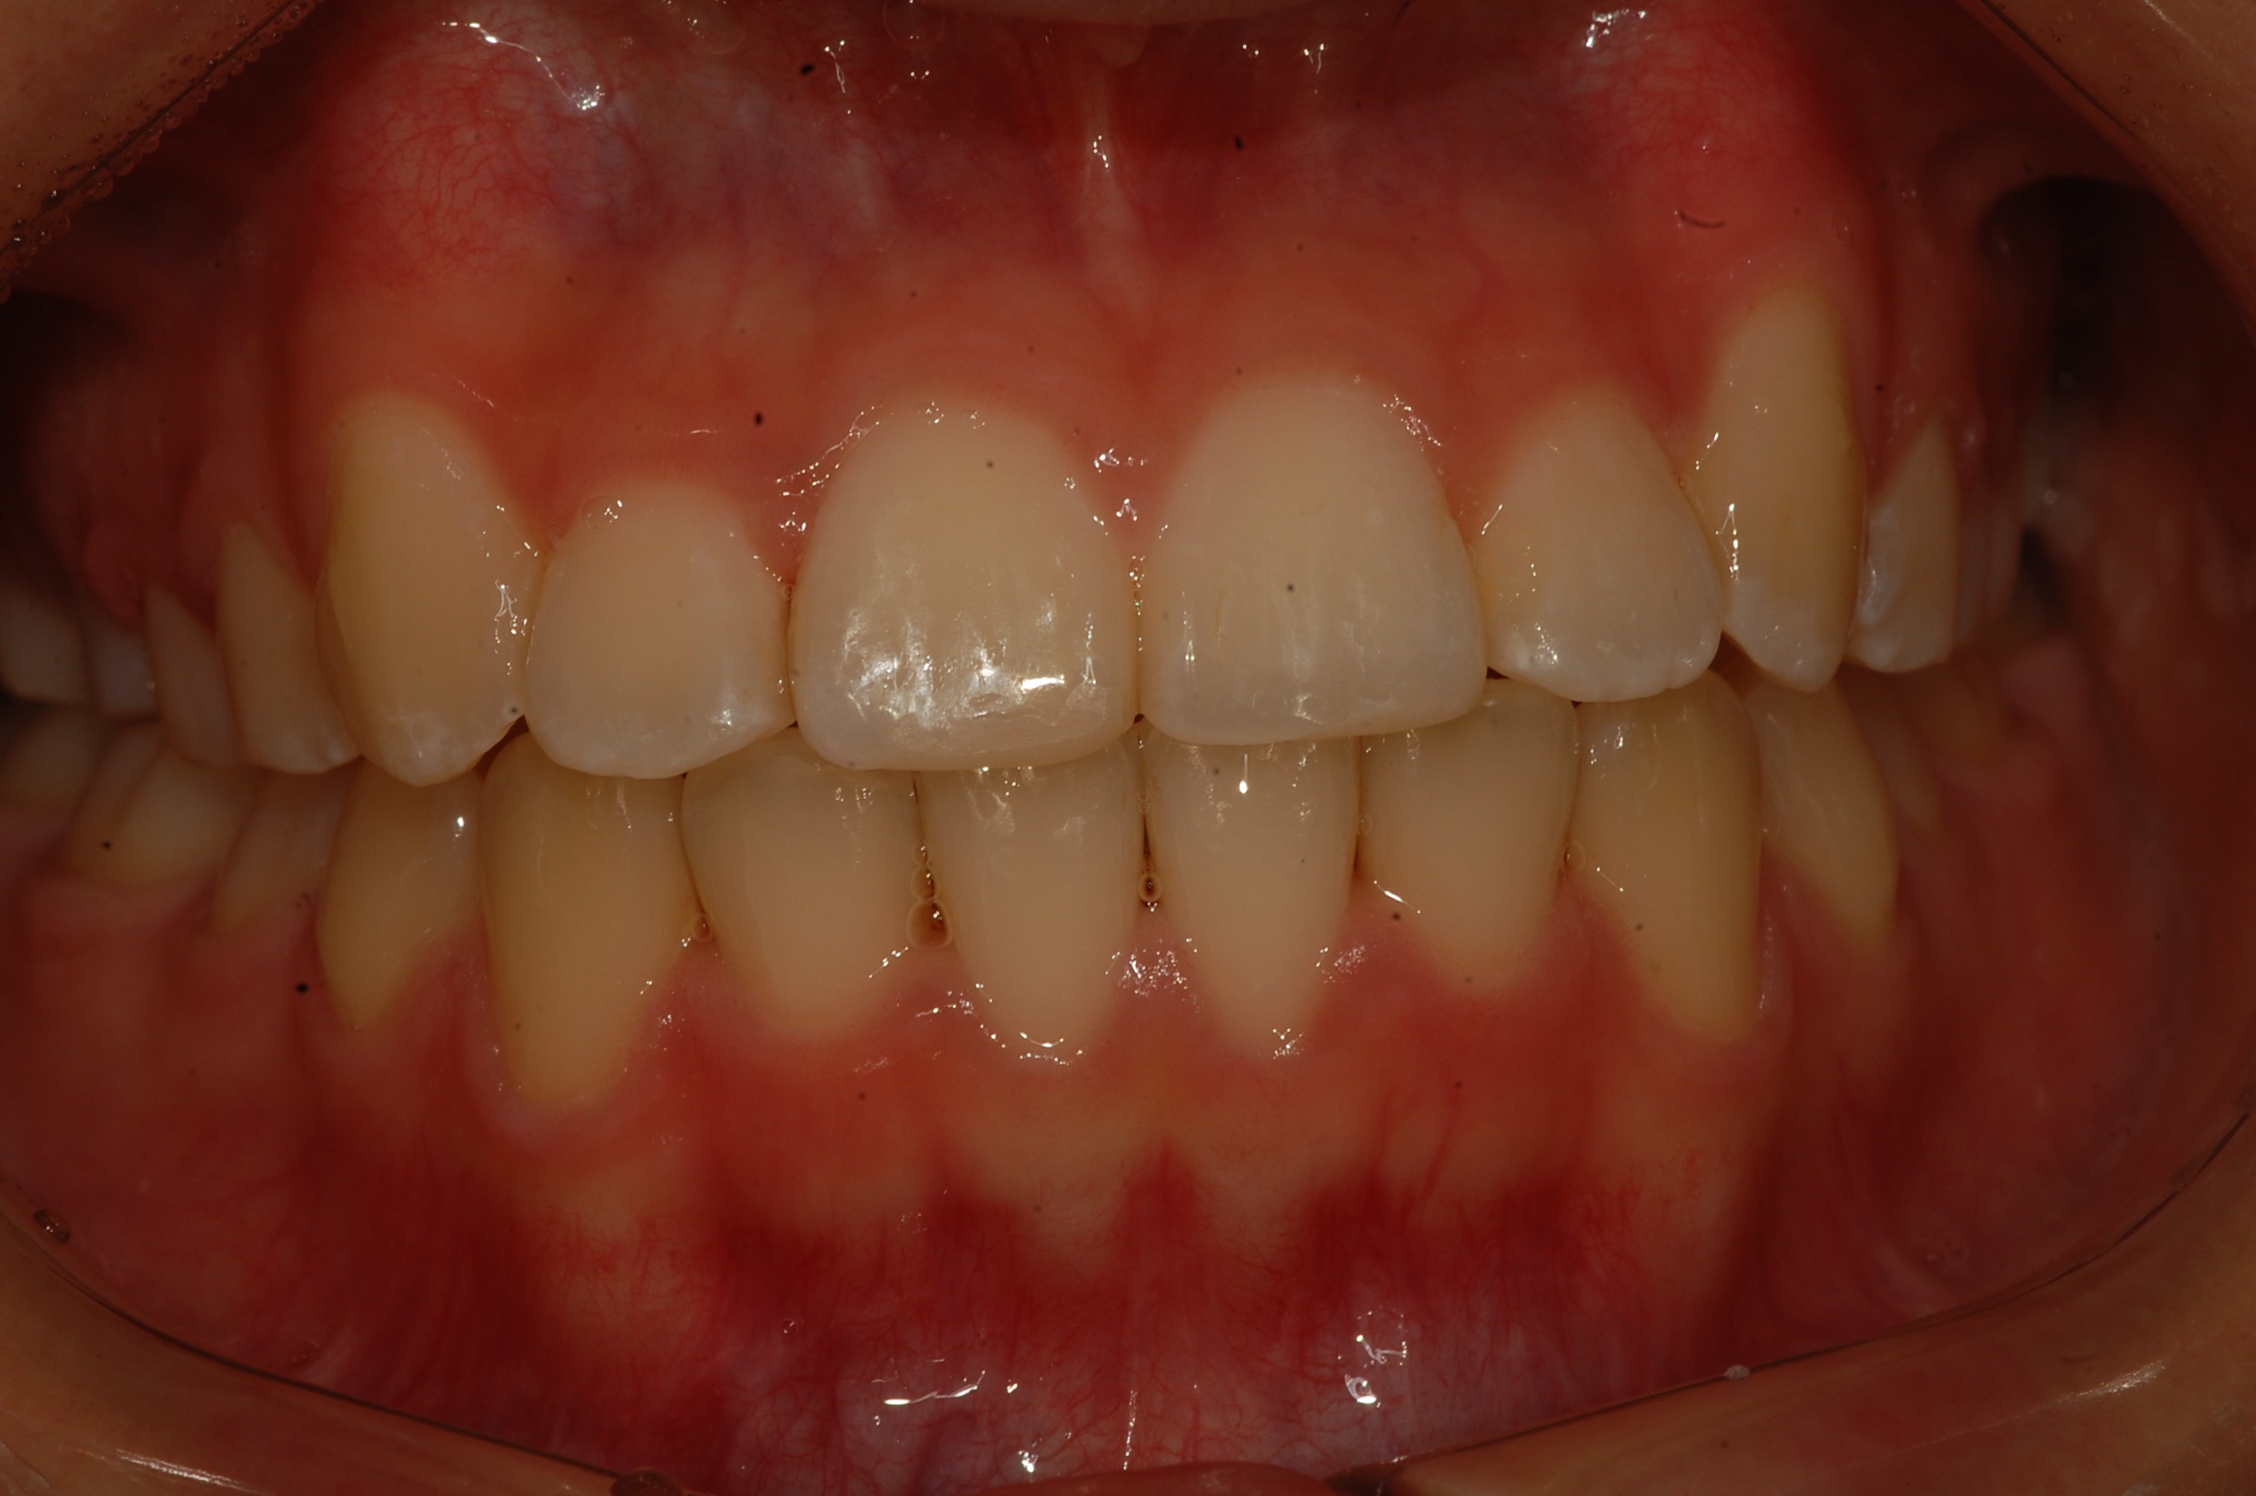

[치아교정] 제목 : (교정)비발치 총생 치료

심한 총생에서도 발치 없이 교정치료